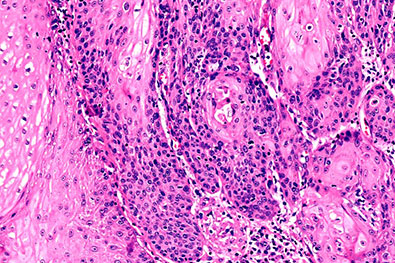

Extensive Cancer Databases

We maintain comprehensive digital libraries for major cancers, including:

Each dataset includes a large number of cases, including benign and normal counterparts, providing rich AI training material.